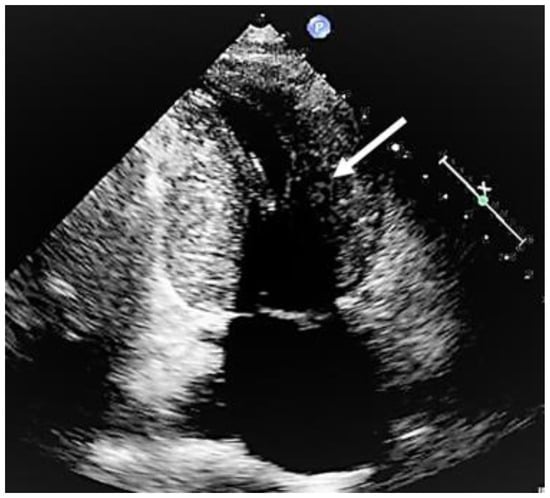

When evaluating the presence and severity of obstruction in HCM, a systematic assessment of all the components of the mitral valve apparatus via 2D echocardiography is required. This technique allows a visualization of the presence and distribution of LV hypertrophy, the presence of SAM, elongation of mitral valve leaflets, displacement of papillary muscles, laxity of tendon cords and LVOT diameter reduction (Figure 2). In addition, 2D echocardiography allows a diagnosis of MCO via the observation of a typical hourglass appearance of the LV due to systolic septal contact with the anterolateral wall, which induces sphincter-like cavity obliteration, creating two distinct (basal and apical) LV chambers (Figure 5). In addition, 2D echocardiography allows a visualization of the presence of an apical aneurysm and any thrombotic formation. In this setting, contrast echo may also be helpful for the correct diagnosis.

Figure 5. Mid-cavity obstruction; typical hourglass appearance of left ventricle (arrow).